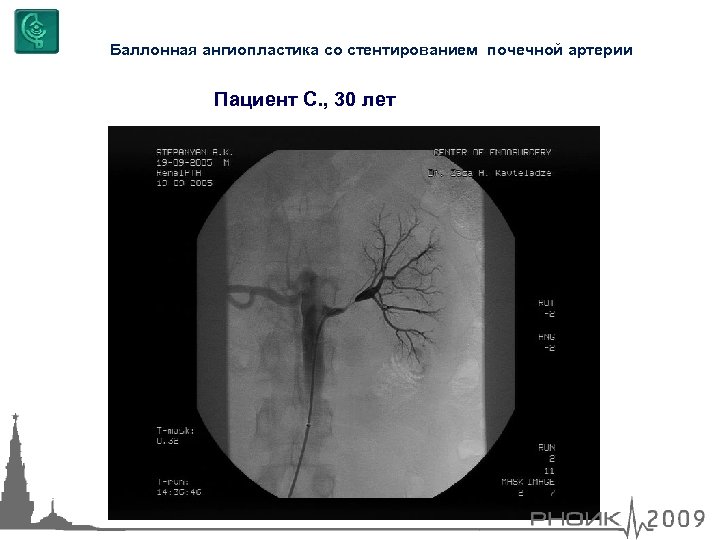

Баллонная ангиопластика со стентированием почечной артерии Пациент С. , 30 лет

Баллонная ангиопластика со стентированием почечной артерии Пациент С. , 30 лет

Баллонная ангиопластика со стентированием почечной артерии Пациент С. , 30 лет

Баллонная ангиопластика со стентированием почечной артерии Пациент С. , 30 лет